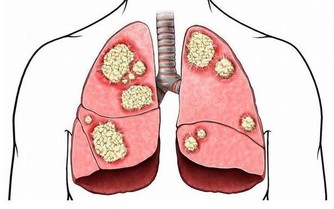

但是如果這些牙結石不能得到及時清理,久而久之,牙結石會一步步往齦下侵蝕,

最後導致牙槽骨萎縮,牙齦退縮,這也是引起牙齦萎縮的一大因素。